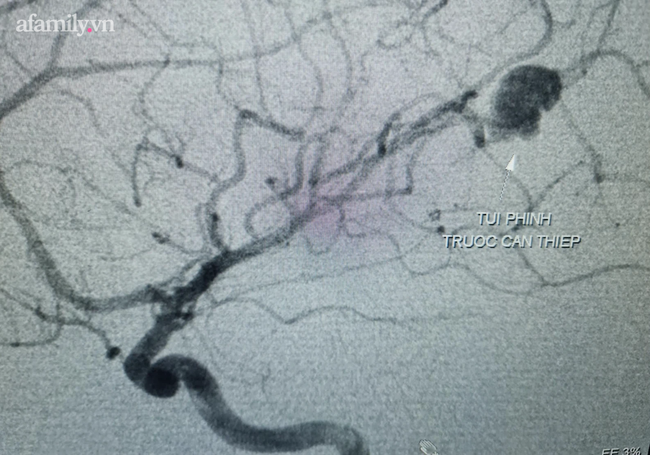

29/07/2021 16:40Bé trai mới 11 tuổi đã bị vỡ túi phình mạch máu não nguy kịch được các bác sĩ cứu sống

Ngày 28/7, BS CK2 Phạm Thanh Phong, Phó Giám đốc Bệnh viện Đa khoa Trung ương Cần Thơ (BVĐKTƯ CT) cho biết, các bác sĩ nơi đây vừa cứu thành công một trường hợp bệnh nhi có túi phình mạch máu não vỡ.

Bệnh nhi là bé T.T.N.B. (11 tuổi, quê thành phố Bạc Liêu) được tuyến trước chuyển đến BVĐKTƯ CT vào chiều tối 17/7 với tình trạng xuất huyết nội sọ vùng thái dương trái.

Sau khi nhập viện, bệnh nhi được chỉ định chụp cộng hưởng từ sọ não, ghi nhận xuất huyết não vùng thái dương trái giai đoạn bán cấp nghi do dị dạng động tĩnh mạch.

Bệnh nhân có tình trạng huyết áp tăng và sốt, được điều trị nội khoa tích cực. Sau đó, các bác sĩ đã quyết định chụp mạch máu não bằng kỹ thuật DSA (chụp mạch máu kỹ thuật số xóa nền) để chẩn đoán xác định.

Kết quả chụp cho thấy tình trạng xuất huyết não ở bé là do túi phình mạch máu não vỡ.

Ngày 26/7, bệnh nhi được chỉ định nút phình mạch máu não số xóa nền DSA.

Các bác sĩ sử dụng 1 ống thông nhỏ, luồn từ động mạch đùi của bé đưa ống thông lên đến tận các mạch máu não nơi có túi phình và thả vào 1 kết cấu đặc biệt gọi là coil nhằm bít túi phình và nút kín chỗ chảy máu.

Quá trình can thiệp đã diễn ra khá thuận lợi và bít được hoàn toàn túi phình sau 45 phút can thiệp.

TS.BS Hà Tấn Đức, Trưởng khoa Đột quỵ cho biết, đây là ca đầu tiên BV áp dụng kĩ thuật can thiệp nút phình mạch máu não số xóa nền DSA ở trẻ em.